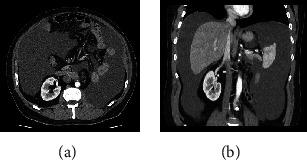

Chylous ascites is an uncommon complication after surgery that can result in malnutrition and immunodeficiency. Therefore, surgical interventions are reserved for refractory patients, and the primary success factor for these interventions is locating the point of leakage, which is often tricky. We describe a case of a 56-year-old male with chylous ascites after laparoscopic radical nephrectomy and lumbo-aortic lymphadenectomy for kidney cancer. The patient was initially managed with dietary modifications and drainage placement. Afterward, lymphography with Lipiodol, percutaneous embolization of the leakage point, and total parenteral nutrition were established. Finally, the patient underwent laparoscopic repair after identifying the leakage point by injecting methylene blue through an inguinal node. Complete resolution was achieved, and no complications related to the procedure were recorded. Intranodal methylene blue injection can be an invaluable tool to identify the point of leakage in selected patients to improve the outcomes of surgical repair of refractory chylous ascites.

乳糜性腹水是手术后一种罕见的并发症,可导致营养不良和免疫缺陷。因此,手术干预仅适用于难治性患者,而这些干预的主要成功因素是找到漏点,这通常很棘手。我们描述了一例56岁男性患者,在因肾癌行腹腔镜根治性肾切除术和腰主动脉淋巴结清扫术后出现乳糜性腹水。患者最初采用饮食调整和放置引流管进行处理。随后,进行了碘油淋巴造影、漏点的经皮栓塞以及全胃肠外营养。最后,在通过腹股沟淋巴结注射亚甲蓝确定漏点后,患者接受了腹腔镜修复。腹水完全消退,且未记录到与该手术相关的并发症。在选定的患者中,经淋巴结注射亚甲蓝可能是一种非常有价值的工具,有助于确定漏点,从而改善难治性乳糜性腹水手术修复的效果。